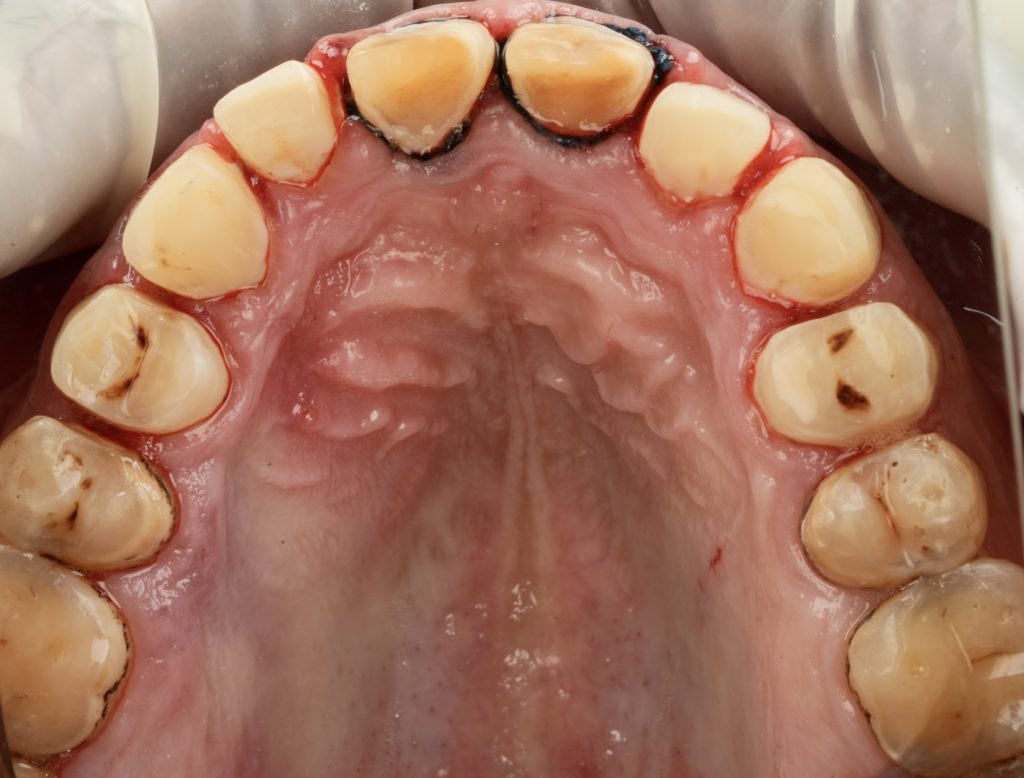

The patient sought esthetic improvement for uneven incisal edges, discolored anterior teeth, and disproportionate gingival display (Fig 1). A digital smile simulation and mock-up try-in were performed to assess tooth proportion, midline alignment, and incisal curvature. The plan prioritized enamel conservation and optical harmony.